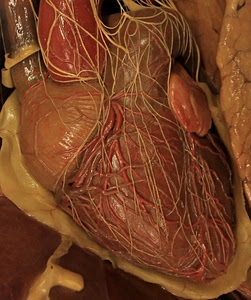

239° Modello di cuore & dintorni

Voto: 21.04 |